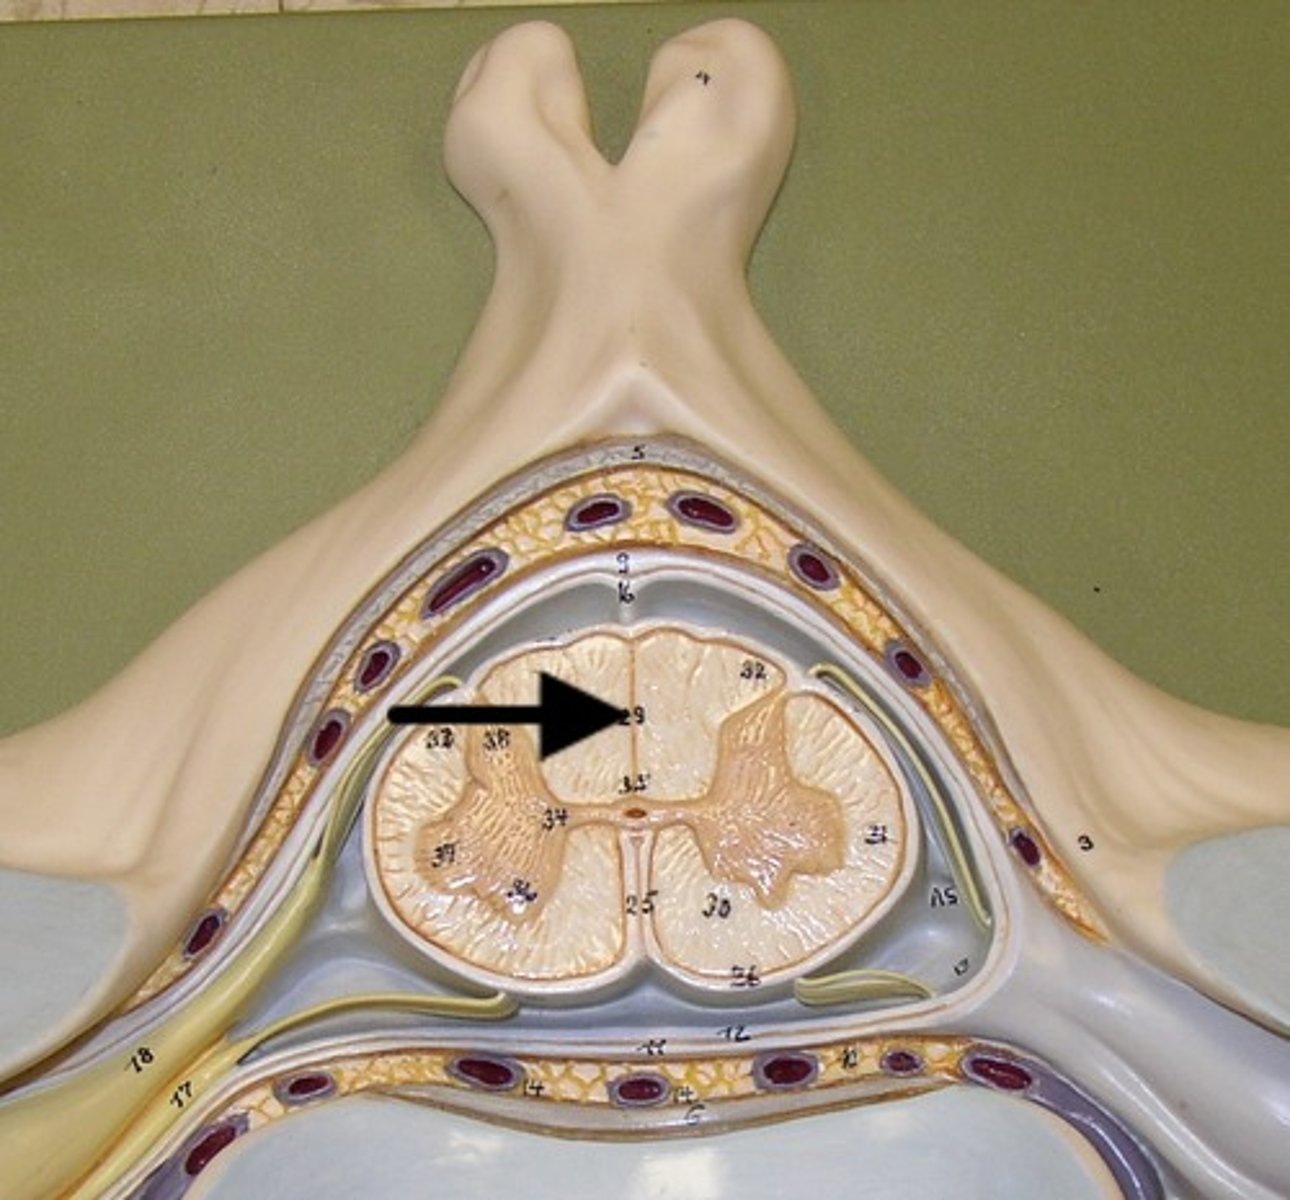

posterior median sulcus

posterior white column

anterior white column

lateral white column

posterior gray horn

anterior gray horn

lateral gray horn

gray commissure

Part of grey matter connecting the two halves of the grey matter in spinal cord

central canal

Hole in the center

Name this passageway